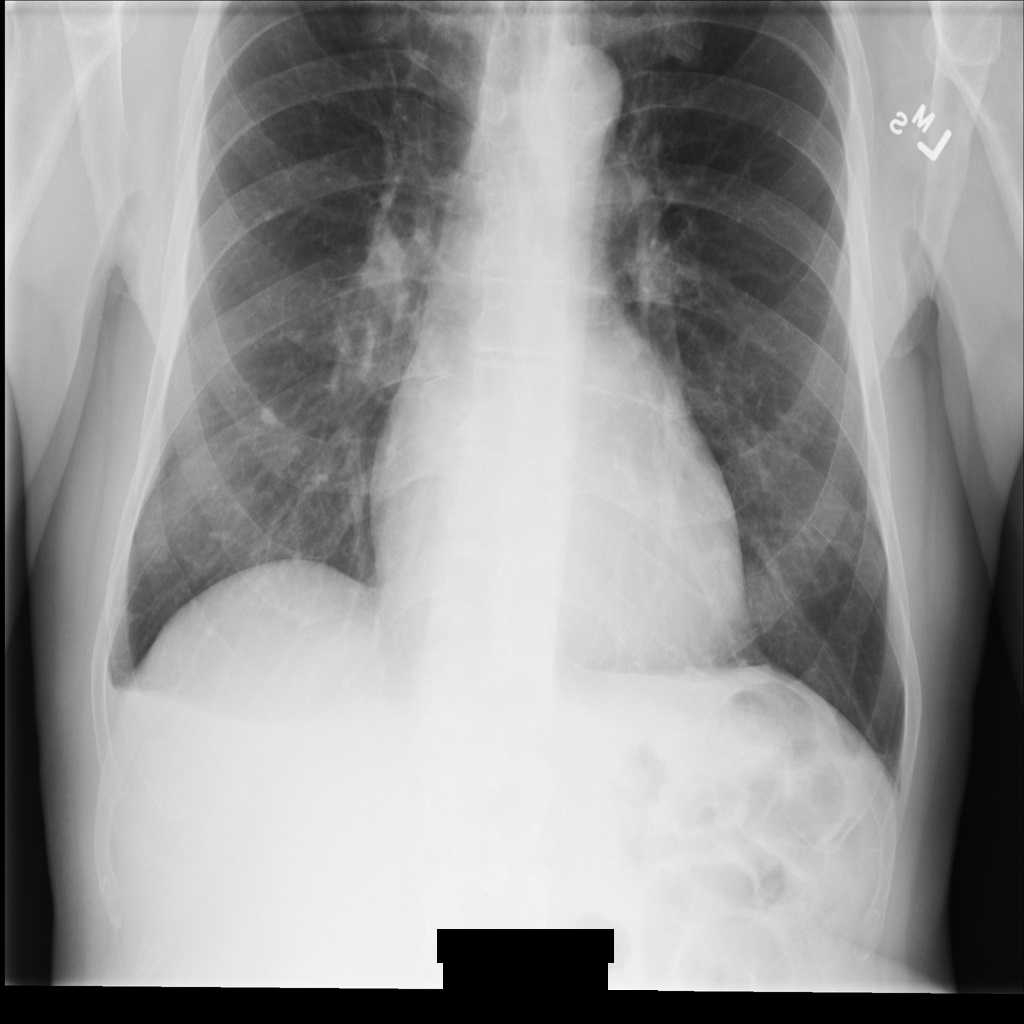

Sample image

Some samples in this page contain an output of the de-identified image. Each sample uses the following original image as its input. You can compare the output image from each de-identification operation to this original image to see the effects of the operation:

xray_original